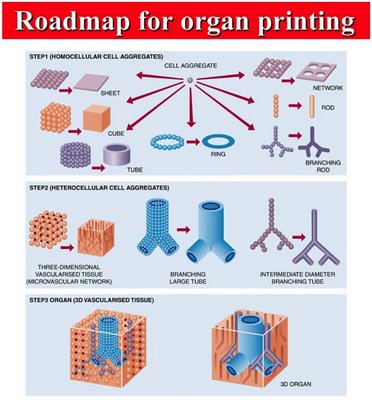

Organ Printing Pondered

We encountered several reports dealing with the fantastic idea of printing human organs using 3D printing technology. The premise is to deposit cells in the appropriate shape. Various prototypes have been attempted, including liver tissue, branched vascular trees and cartilage. The bad news is that the experts predict it could be decades before such… Continue reading Organ Printing Pondered

Can We Print a Human?

That’s the question being considered by Duncan Graham-Rowe of New Scientist. The premise is whether the components that make up each of us can be replaced using modern technology. Replacement bones are discussed, and as we’ve talked about before, they are a very good candidate for 3D print technology: they are relatively small 3D objects… Continue reading Can We Print a Human?